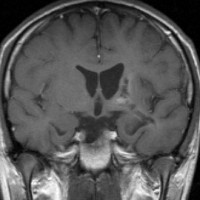

2000年頃の例です。閉塞性水頭症を併発する松果体部germinoma:左のMRIは発症時のものです。定位的生検術で確定診断して脳室ドレナージを留置しました。1コースのICE化学療法直後,生検術から6日目のMRI(中央)では腫瘍はほぼ消失し,水頭症は改善したのでドレナージを抜去しました。4コースの化学療法後(右側)に24Gyの全脳室照射を加えました。